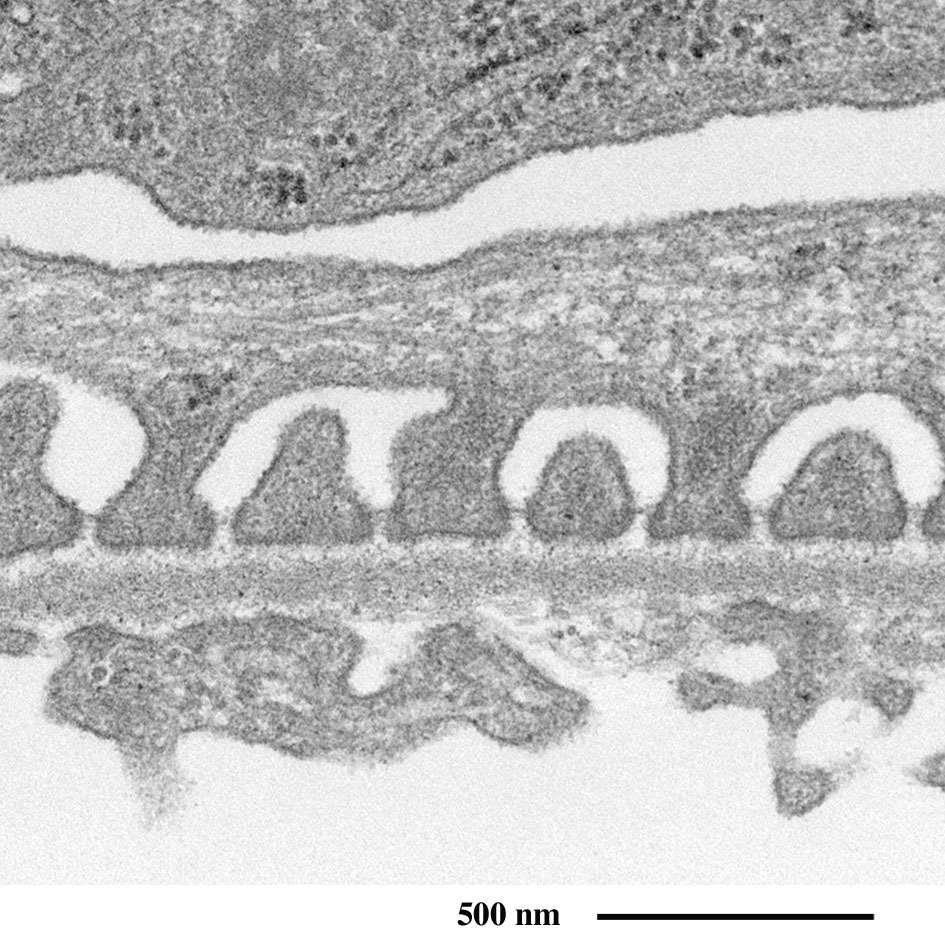

肾小球的有孔毛细血管

(血管壁的横断面)

红色:血管内腔、蓝色:血管内皮细胞、绿色:足细胞